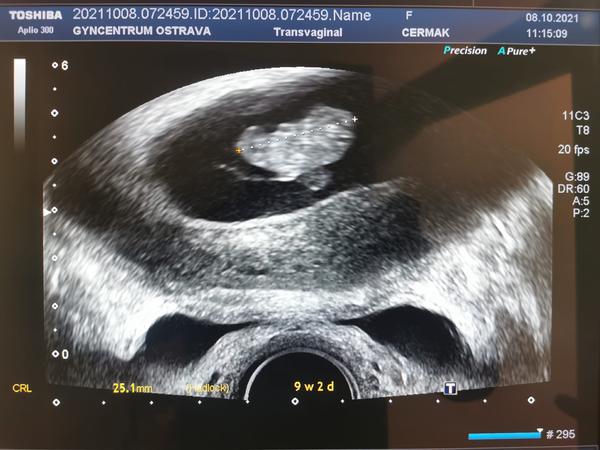

@stastnamatka07 Moc gratuluji k pozitivnímu testu ❤️ Jinak já to měla tak samo, ale testovala jsem dříve kvůli injekci Ovitrelle abych věděla, kdy už ji v tele nemám. A výsledek takových testu co máš teď ty je na obrázku 9+2 😊 Akorát si myslím, že jdeš k lékaři hodně brzy, Ja otěhotněla 20.8. A na kontrolu jsem šla až 20.9. 😊 každopádně přeji ať je vše v pořádku ❤️